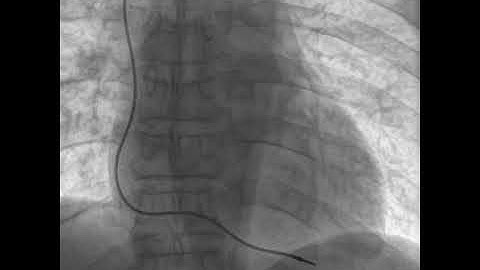

Permanent Pacemaker Implantation